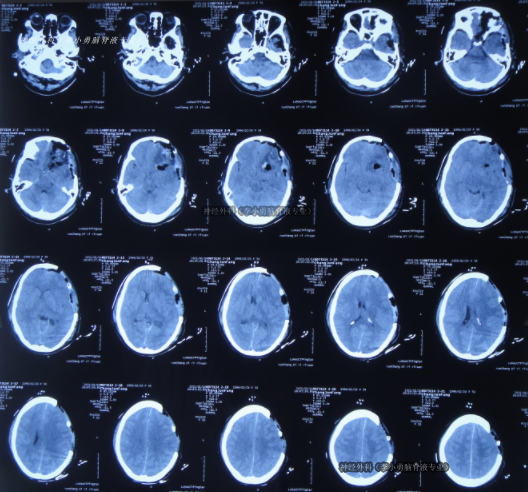

左额叶-胼胝体肿瘤卒中 侵犯对侧额叶 急诊开颅切除 镜下全切